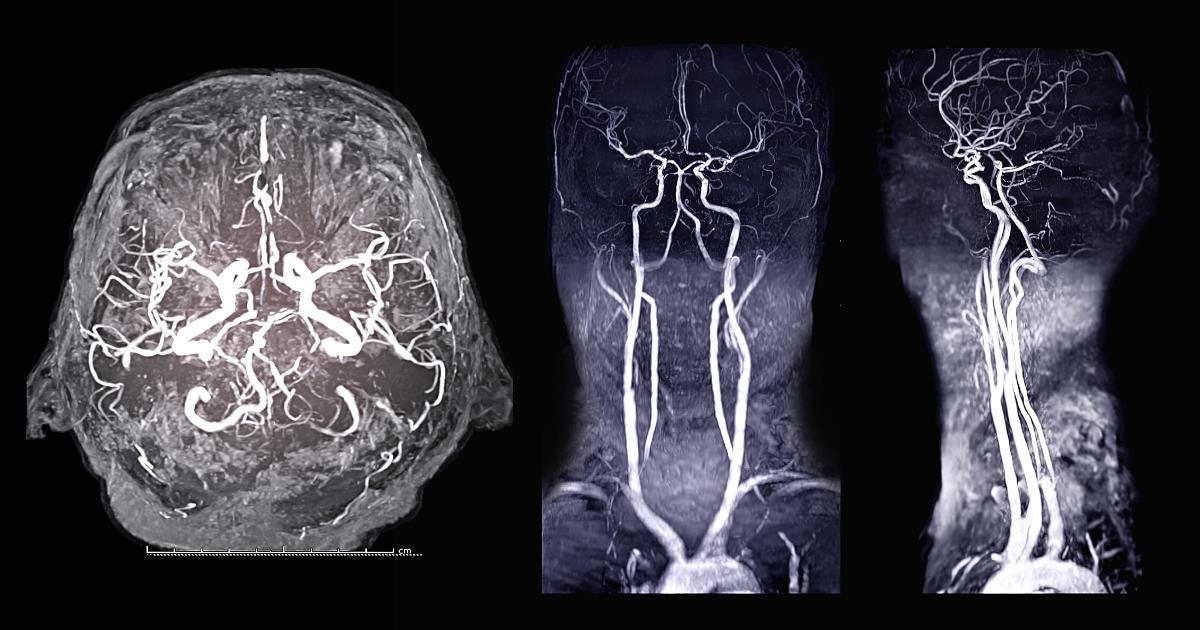

Resonance Angiogram (MRA) Artery Test OneWelbeck What Is A Mri Scan With Contrast Why do i need contrast? In particular, tumor growths or. An mri with contrast provides great detail of your internal organs and soft tissue and can detect disease, infection, and other ailments. What is an mri with contrast? The mri scan with contrast works by highlighting specific parts of your soft tissue, helping the radiologist come up with a diagnosis. What Is A Mri Scan With Contrast.